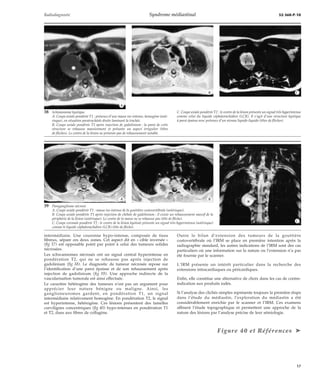

10 Tératome médiastinal bénin avec adhérence péricardique

à l’intervention.

A. Thorax de face : opacité à limite externe nette effaçant

le bord droit du coeur (signe « de la silhouette »).

B. Tomodensitométrie (TDM) : masse de faible densité

(5 unités Hounsfield [UH]) refoulant l’oreillette droite

dont la paroi est mal analysée en raison des battements

cardiaques.

C. Imagerie par résonance magnétique (IRM) : coupe

frontale pondérée en T1 montrant un signal hyperin-tense

et une formation nodulaire murale (flèches).

D. IRM : coupe axiale pondérée T1 montrant l’interrup-tion

du péricarde antérieur (flèches) au contact de la

tumeur.

· Signe de la silhouette [14]

Il précise le siège de la lésion, qui se situe dans le même plan que la

structure dont la silhouette a disparu (coeur, aorte, diaphragme)

(fig 10).